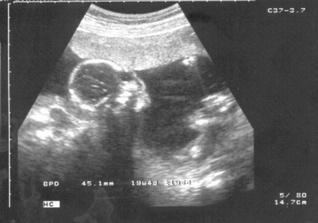

Samuelka jsem viděla, moc vyrostl a už vypadá jako macaté miminko (má 1500 gramů), i když ještě pořád má dost času...Je krásný, při utz na mě koukal a otvíral pusinku 🙂 Jen má stále dupku dole. Snad se stihne otočit. Kontrola 19.11.

4. ledna - tak jsme to zdárně dotáhli až do konce, začínáme 40. týden! 🙂 Vše je v pořádku, během ozev jsme naměřili zhruba 130 tepů/min., takže nás paní doktorka poslala do porodnice na překontrolování, kde proběhlo vše v pořádku, ozvy OK, průtok pupečníkem OK, Samuelek váží zhruba 3kg a je hlavičkou dolů, porodní cesty připraveny, čípek na půl cm, prý stačí kontrakce a je to 🙂 Takže už jen čekáme...Na kontroly už budu chodit jen do porodnice.